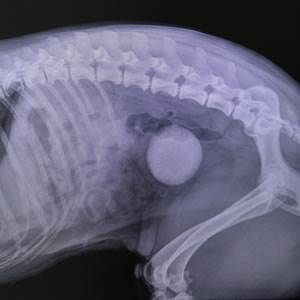

Vets save dog with bladder stone ‘the size of an orange’

Twelve-year-old crossbreed, Sheba, was immediately rushed into theatre for emergency surgery after x-rays detected a huge stone, which could easily have caused a fatal blockage.

“The life-threatening stone was over 7cm wide - bigger than a large bar of soap - and was completely whole when we removed it. It’s very rare for a stone to stay intact as they normally fragment.”